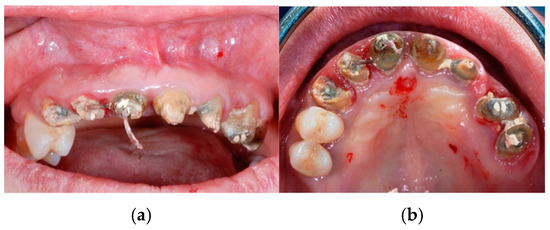

Figure 8. Clinical view (frontal in (a) and occlusal in (b)) of the upper maxillary arch before implant placement.

Figure 9. Full-thickness mucoperiosteal flap elevation.

Figure 10. Using a dedicated core drill (a) with the aid of a surgical guide (b), biopsies of regenerated bone were performed in four sites for histomorphometric analysis of post-extractive sites (c,d).